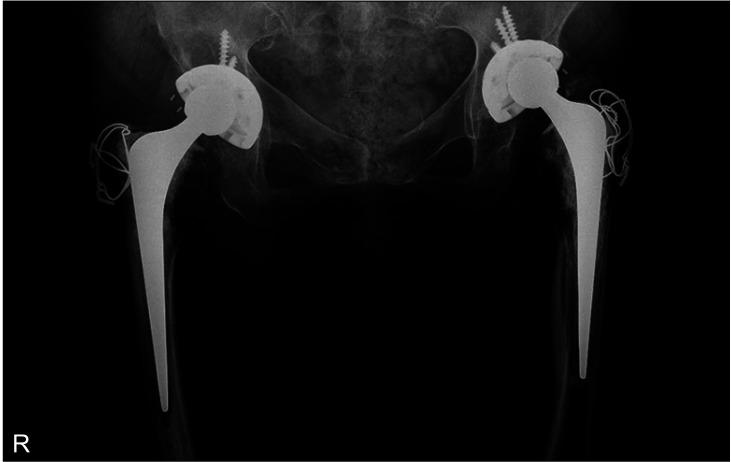

Cemented stems and cementless cups with the conventional polyethylene liner were used in bilateral hips of a single patient. In the other cases, cementless implants were used with ceramic-on-ceramic bearings. The mean HHS improved from 34.8 preoperatively to 92.5 postoperatively. Polyethylene liner wear and osteolysis were observed in 1 patient with cemented stems. Radiolucent lines were observed in 2 different cases. However, the femoral stems remained stable. There were no surgery-related complications except heterotopic ossification during follow-up.

Despite the several surgical considerations, the mid- to long-term clinical and radiological outcomes of THA in HME patients were satisfactory. The abnormal, wide mediolateral diameter of the proximal metaphysis should be considered in selecting and inserting the stem with adequate anteversion. Leg length discrepancy was also common, so teleradiographs should be obtained before surgery. Intraoperative leg length evaluation might be difficult due to the morphologic changes in the proximal femur after mass excision and individual bone length differences.